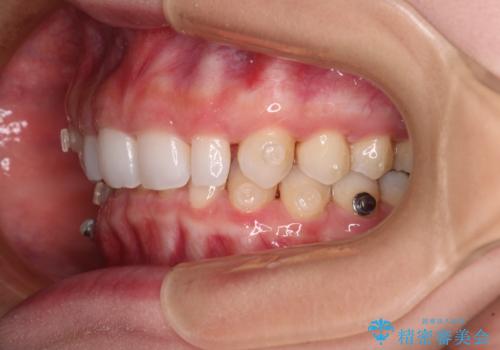

前歯のデコボコと小さい歯を改善 インビザラインとオールセラミッククラウン

- 前歯のデコボコと左右の矮小歯を気にして来院された患者様です。

矮小歯の前後にスペースを作るようにインビザライン矯正治療を計画し、矯正治療後にオールセラミッククラウンによる補綴治療を行うこととしました。

アンカースクリューを用いて上顎歯列全体を後方移動させ、極力過蓋咬合も改善されるよう計画しました。

インビザラインは長時間装着を自己管理する必要がありますが、残念ながら十分な時間の装着を行うことができませんでした。

何とか矮小歯を改善するスペースを作ることはできましたが、過蓋咬合を改善するには至りませんでした。